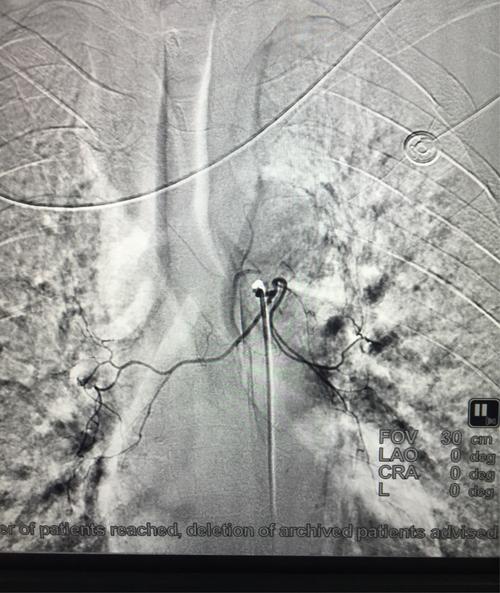

右支气管动脉造影见右肺下叶支气管动脉,扭曲,且造影剂直接溢入支气管

右侧支气管动脉经过造影,发现少量造影剂外溢,证实血管破裂出血